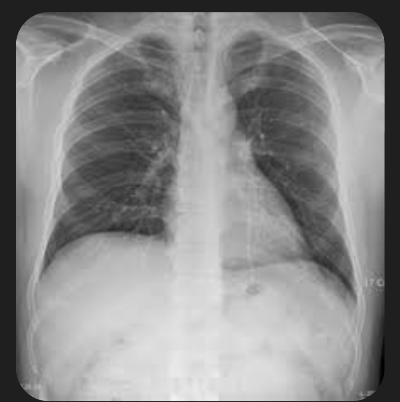

5. 폐렴 증상

폐렴 증상은 질환이 진행되면서 다양하고 심각하게 나타납니다. 주요 증상으로는 고열, 후두통, 가래를 동반한 강한 기침, 흉통, 호흡곤란, 빠른 호흡 등이 있습니다. 가래는 화농성으로 노란색이나 녹색을 띕니다.

sns에 올라온 어떤 60대의 글을 보니 며칠전부터 가래가 끓고 후두통이 있었으며 마른 기침을 계속 했었는데, 감기가 세게 왔구나 생각했다고 합니다. 그러다 갑작스러운 흉통과 호흡곤란으로 응급실을 찾게 되었습니다. 결국 폐렴 진단을 받았는데요. 초기 치료가 지연되면서 증상이 악화되었지만, 집중 치료로 완치할 수 있었습니다.

폐렴 증상이 심각해지면 입원 치료가 필요하며, 면역력이 약한 경우 합병증이 생길 가능성이 큽니다. 폐렴 치료는 증상에 따라 달라지므로 초기에 의료진의 지시를 따라야 합니다.